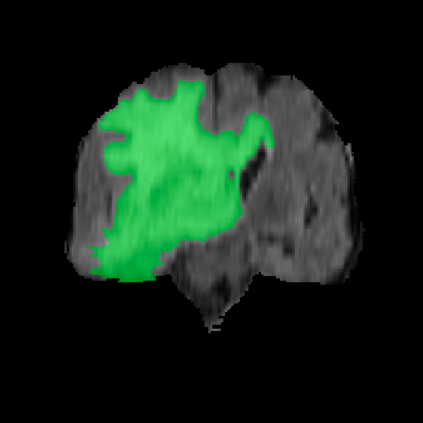

Automatic and accurate tumor segmentation on medical images is in high demand to assist physicians with diagnosis and treatment. However, it is difficult to obtain massive amounts of annotated training data required by the deep-learning models as the manual delineation process is often tedious and expertise required. Although self-supervised learning (SSL) scheme has been widely adopted to address this problem, most SSL methods focus only on global structure information, ignoring the key distinguishing features of tumor regions: local intensity variation and large size distribution. In this paper, we propose Scale-Aware Restoration (SAR), a SSL method for 3D tumor segmentation. Specifically, a novel proxy task, i.e. scale discrimination, is formulated to pre-train the 3D neural network combined with the self-restoration task. Thus, the pre-trained model learns multi-level local representations through multi-scale inputs. Moreover, an adversarial learning module is further introduced to learn modality invariant representations from multiple unlabeled source datasets. We demonstrate the effectiveness of our methods on two downstream tasks: i) Brain tumor segmentation, ii) Pancreas tumor segmentation. Compared with the state-of-the-art 3D SSL methods, our proposed approach can significantly improve the segmentation accuracy. Besides, we analyze its advantages from multiple perspectives such as data efficiency, performance, and convergence speed.

翻译:医疗图象上的自动和准确肿瘤分解是帮助医生诊断和治疗的高需求,然而,很难获得深学习模型所需的大量附加说明的培训数据,因为人工划定过程往往乏味,需要专门知识。尽管为解决这一问题,已经广泛采用了自我监督的学习(SSL)计划,但大多数SSL方法只侧重于全球结构信息,忽视肿瘤区域的主要特征:局部强度变化和大面积分布。本文提出SOSL(SAR),这是3D肿瘤分解的一种SSL方法。具体地说,设计了一个新的代用任务,即规模歧视,以预先将3D神经网络与自我重置任务结合起来。因此,预先培训的模型通过多尺度投入学习多层次的地方代表性。此外,还引入了一个对抗性学习模块,以学习多种无标签来源数据集的变异表达模式。我们展示了两种下游任务的方法的有效性:i)脑肿瘤分解、ii)Pancreas-剖析(SLA)的精度、3SL(SL)的精度分析方法,以及我们提议的SL(SL)的精度分析方法。